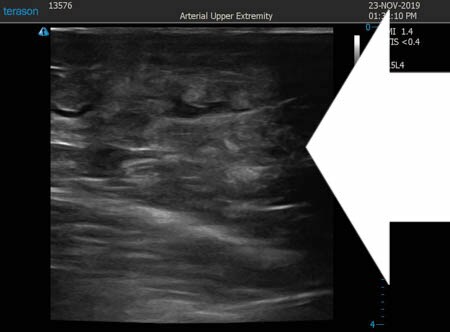

いつものように3Dタッチビュー(超音波)で

皮下脂肪層を評価してみましょう。

左太もも前面。